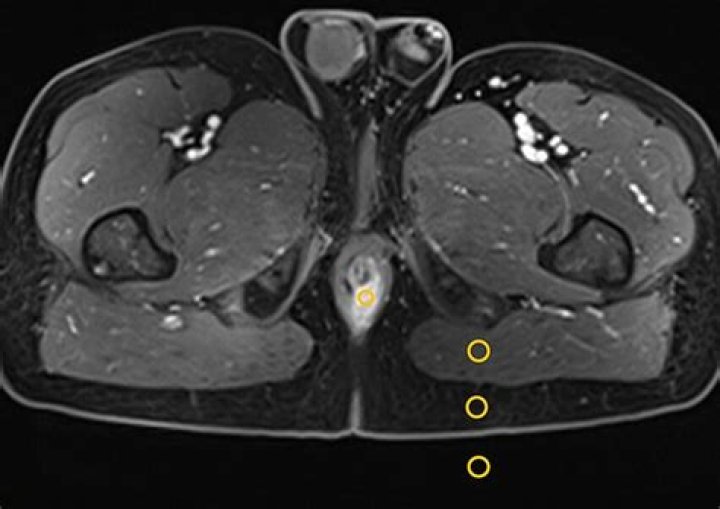

What is CNR MRI?

CNR (contrast-to-noise ratio) is a measure of how distinguishable two structures are from each other. For magnitude images (most commonly used in MRI), the. contrast-to-noise ratio is: CNR = SNR, – SNR. – 0.655.(S, -S2)

How is CNR calculated?

Contrast-to-noise ratio (CNR) is just the ratio of the estimated contrast and noise: CNR = C/N.